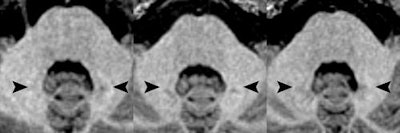

Axial MR images of a patient before (left) and after four (middle) and eight (right) administrations of the macrocyclic GBCA gadoterate meglumine. Location of the hyperintense dentate nucleus (arrowheads) is evident, with the patient's pre-existing hyperintensities due to 14 prior administrations of linear GBCAs. Images courtesy of Radiology.Study strengths

The ratio differences did not vary significantly from 0, meaning there was no increase in T1 signal intensity. The dentate nucleus-to-pons ratio difference between the first and last MR scans was -0.0012 ± 0.0101 (p = 0.4360), while the dentate nucleus-to-middle cerebellar peduncle ratio difference was 0.0007 ± 0.0088 (p = 0.604).